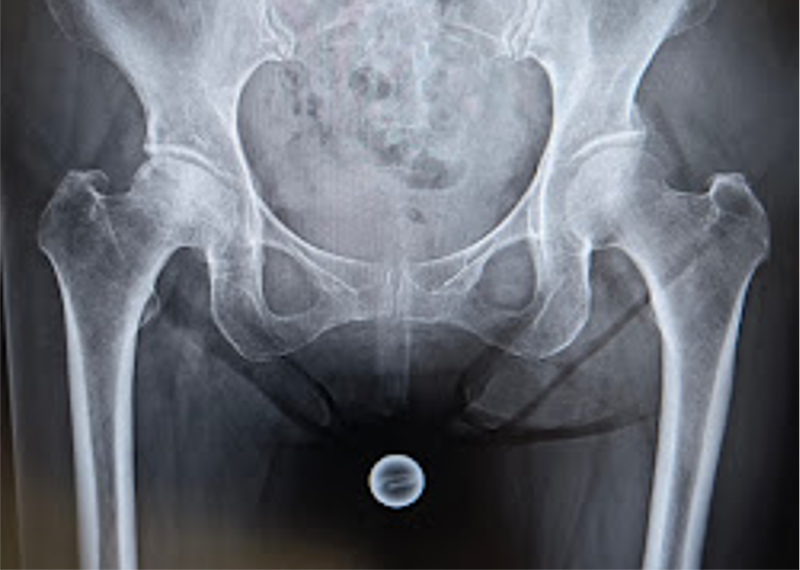

〈手術前のレントゲン〉

当院にて人工股関節全置換術(THA)を施行。アプローチはAMIS(前方最小侵襲手術)で行い、術中に神経ブロックを行い術後の痛みをコントロール、術翌日から歩行器での歩行訓練を開始し術後2日目には杖なしでの歩行が可能となり、スムーズにリハビリを進めることができました。